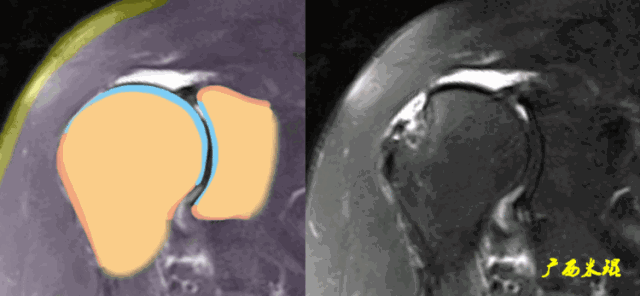

(1)斜冠状位:平行于冈上肌腱长轴,主要评估冈上肌。

正常肩袖的MRI表现

各个序列肩袖均表现为均匀的低信号,是肌腱的延续。

肩袖损伤的MRI分级(Zlaikin)

Grade0:肩袖形态正常,连续性完好,肩袖信号正常。

Grade1:肩袖形态正常,连续性完好,肩袖内信号异常。

Grade2:肩袖连续性存在,形态异常(肩袖变薄/变厚,形态不规则)。

Grade3:肩袖外形异常,连续性中断。

在Zlaikin分级中,0级是正常肩袖,1、2级代表退变,3级为撕裂,也就是真正的肩袖损伤。